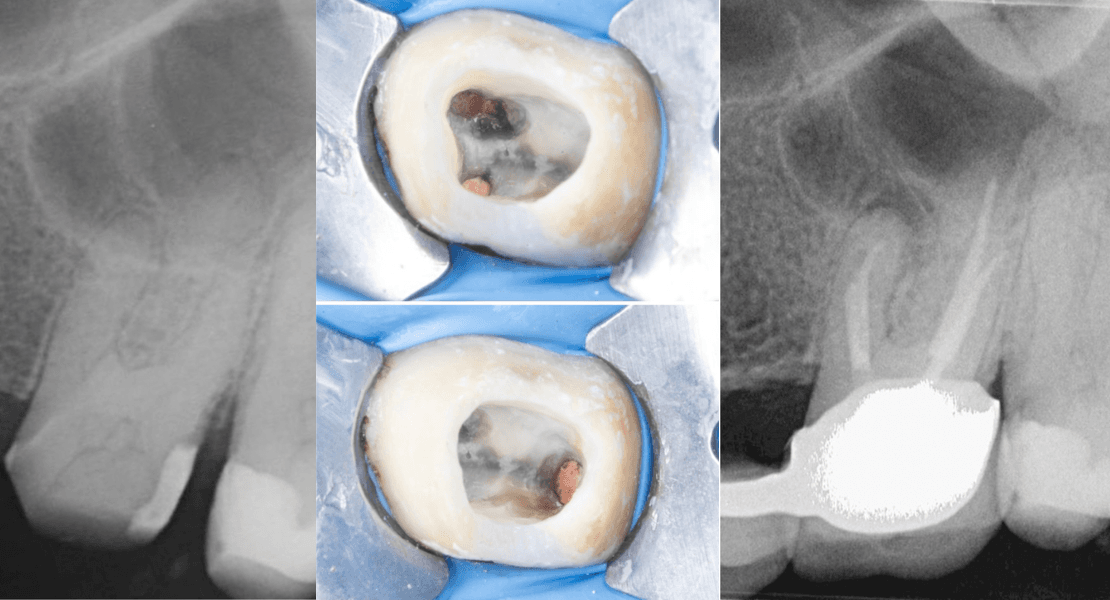

🥉 Dt. Abdullah Özceylan

Apikal Üçlüsünde Kırık Alet ve Basamak Bulunan Dişin Retreatment Tedavisi